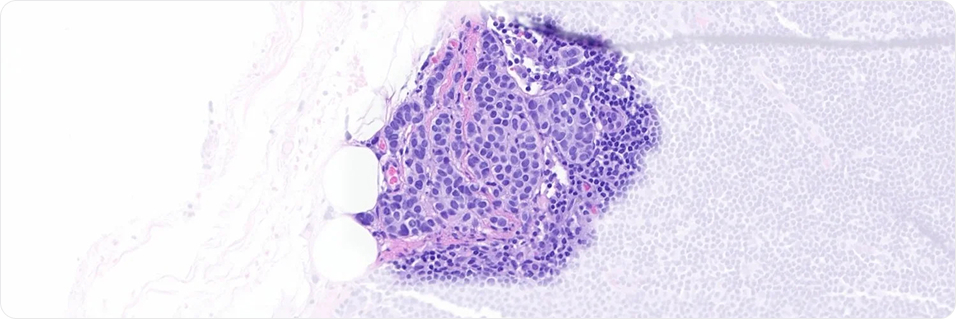

Maximizing Precision in Pathology with AI. The Paige Predict model utilizes H&E images to forecast tissue nucleic acid (TNA) yield, identifying samples at risk of NGS failure1 or those that may need fewer slides for extraction2.

Use of a deep learning model on H&E slides to predict nucleic acid yield for NGS testing

A deep learning model predicts the TNA yield from H&E slides for NGS testing, potentially reducing assay failures and optimizing sample selection for targeted therapies